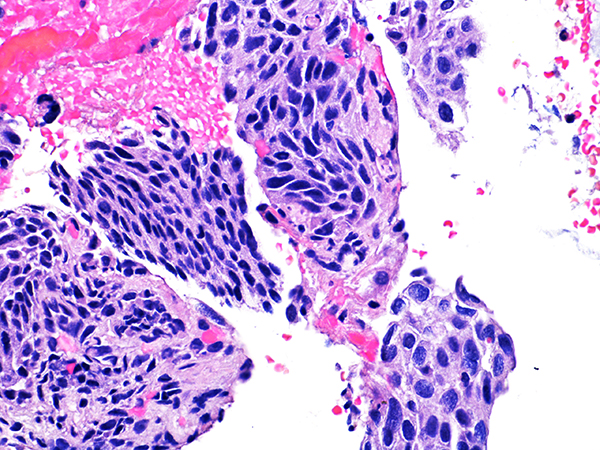

Case 1

Area 1 - Soft Bx CIN 2 40x - High Power |